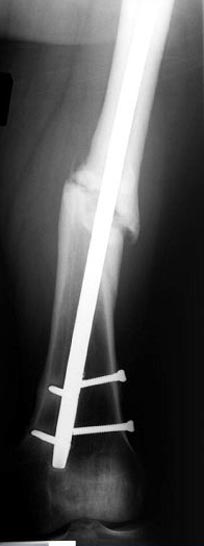

Деформация:

Вальгус- 17 градусов

Рекурватум 5 градусов

Укорочение 2.5см

Ротационно 22 градусов внутренная

Смещение диафиза по поперечнику 75%